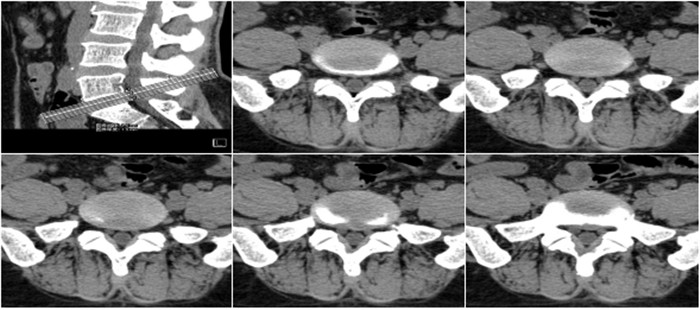

明峰CT搭載了領(lǐng)先的硬件技術(shù)平臺及系統(tǒng),強大的掃描能力可滿足臨床的各種要求,呈現(xiàn)更極致的細節(jié),為各臨床科室提供高品質(zhì)的圖像。薄層掃描,消除部分容積效應,提高各向同性。配合高分辨率算法,有助于細微結(jié)構(gòu)和形態(tài)學顯示。